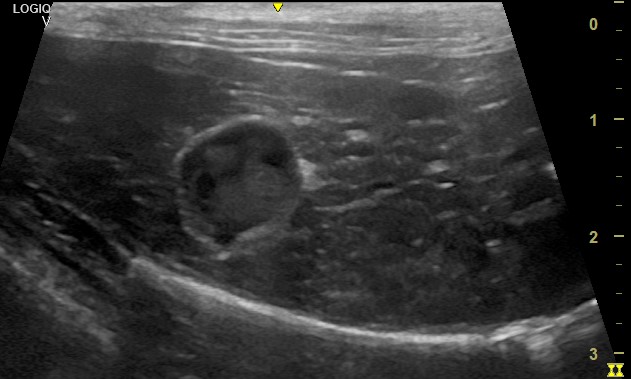

La ecografía abdominal reveló las siguientes alteraciones:

–Riñón izquierdo: presencia de masa en el polo caudal.

-Riñon: Compatible con linfoma de células intermedias-grandes.